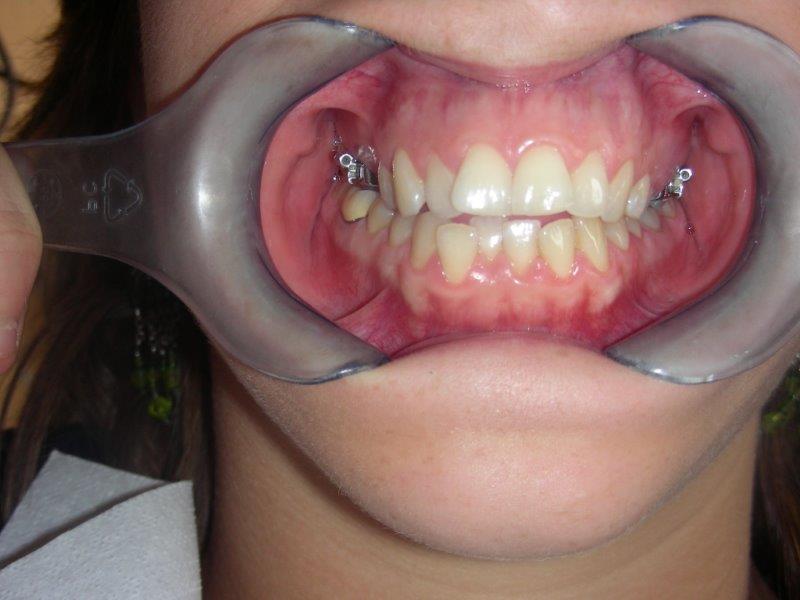

Se puede utilizar enganches (o brackets) que se pegan en las caras de los dientes para desplazarlos haciéndoles deslizarse sobre arcos, hasta obtener una oclusión correcta y estable.

De 13 a 16 años:

Todos los dientes definitivos han salido.

Es más difícil de ganar espacio en las arcadas y por ello, a veces es necesario extraer ciertas piezas.